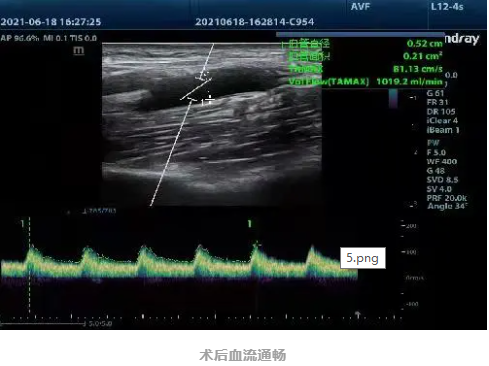

1个多小时后,手术顺利完成。术后,杨伯伯内瘘功能恢复,次日上午顺利进行了血液透析治疗。杨伯伯高兴地说:“感谢洪泉医院的精心治疗,让我可以安心透析。”